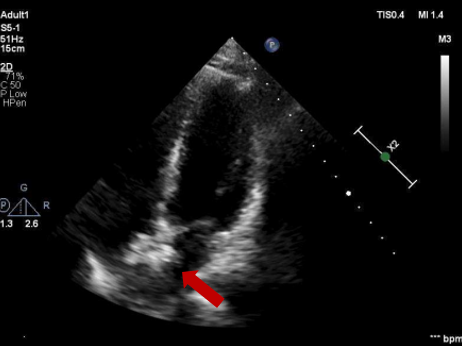

超声报告:房间隔中部连续性中断约6mm,主动脉侧较秃,对侧14mm,距上腔14mm,距下腔17mm,距二尖瓣14mm,距房顶14mm,房间隔总长35mm;室间隔连续完整,未见动脉导管,弓降部通畅;三尖瓣环扩大,各瓣叶形态活动尚可; 右心饱满,左心正常,室壁厚度正常;多普勒检査:房水平左向右双期分流,流速1m/s,压差4mmHg,三尖瓣轻度反流,估测肺动脉收缩压26mmHg,左房内可见四支肺静脉汇入; 心功能:室间隔居中,未见节段性异常。

超声多切面确认

封堵器骑跨房间隔两侧

五腔心切面

剑下双房心切面

四腔心切面

主动脉短轴切面

封堵器呈“Y”字形牢牢抱住主动脉,夹持缺损